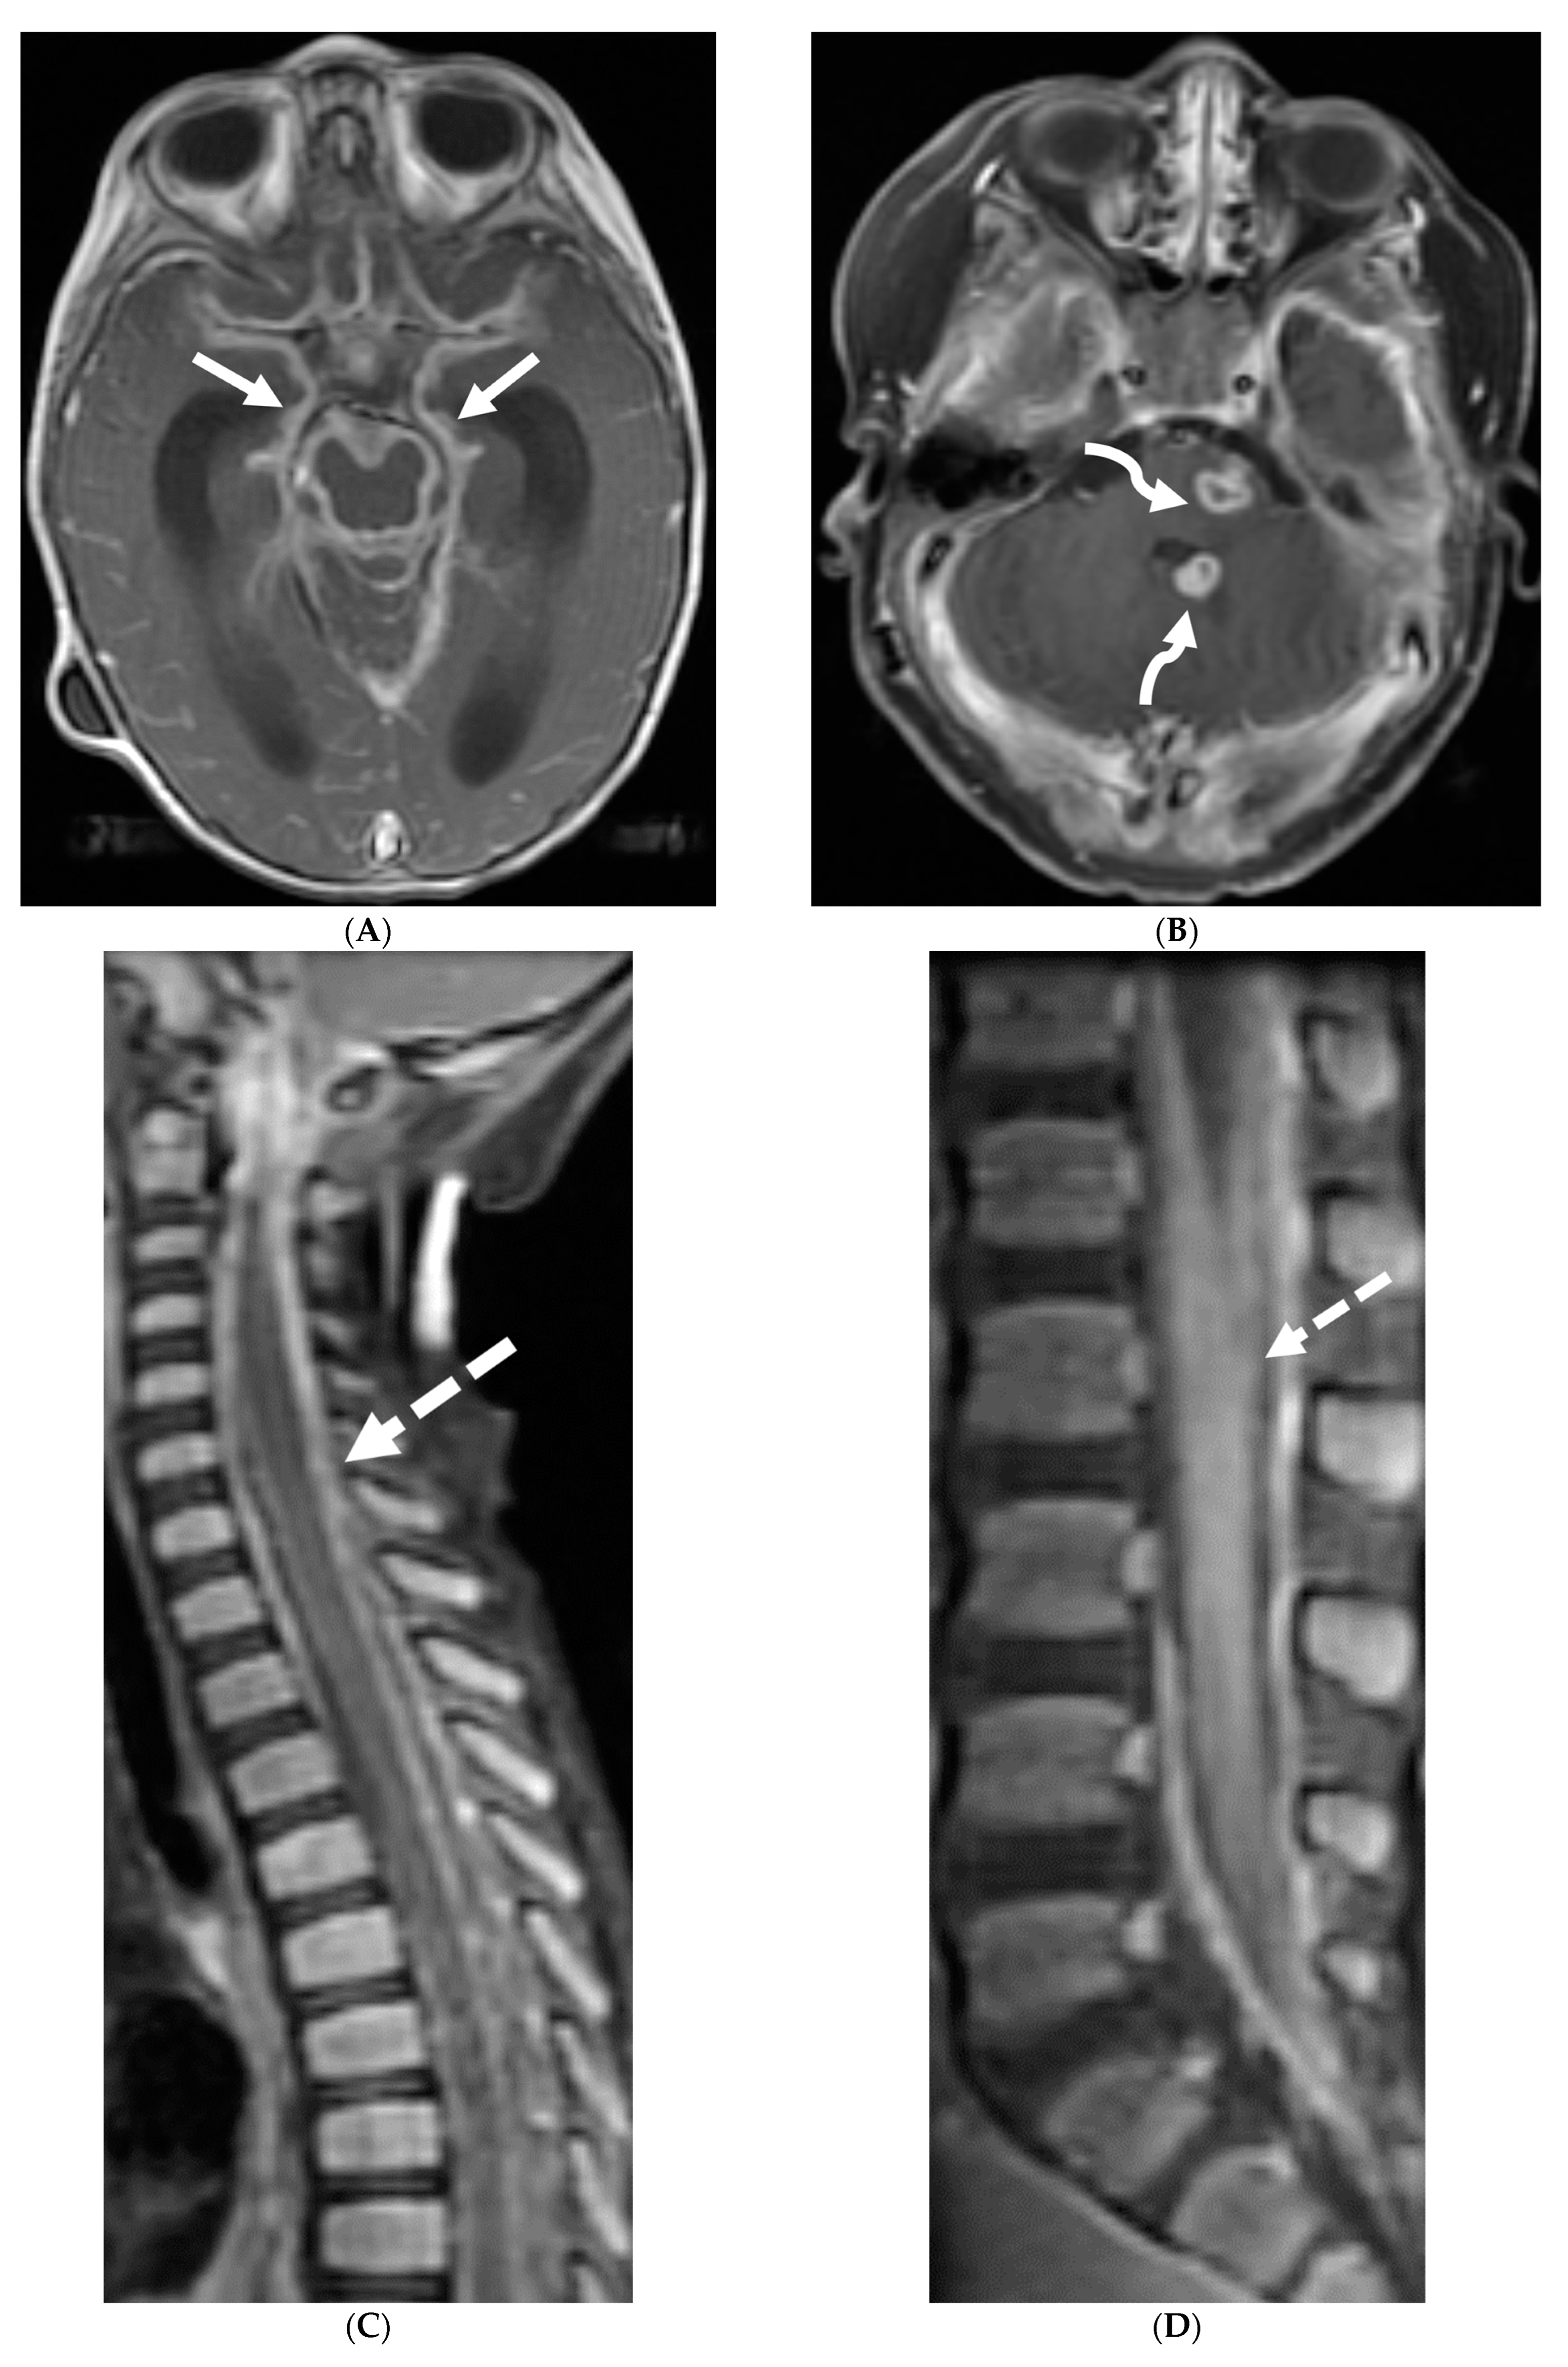

Marked focal nodularity and mass effect causing a deformed contour on the spinal cord favor a neoplastic process (Figure 7) [62]. Accurate staging is crucial as the presence of leptomeningeal or multifocal disease have implications on radiotherapy fields and total dose. Additionally, PET-CT scan assists in evaluating for an extracranial primary site [63].

Figure 7.

3-year-old boy with 2 weeks history of headache and vomiting. Axial FLAIR (A), post contrast axial T1 FS (B) and sagittal 3D inversion recovery (C) images demonstrate FLAIR hyperintensity in the interpedencular cistern (curved arrow) and mild hydrocephalus. Extensive meningeal enhancement most prominent at the skull base, basal cisterns, and Sylvain fissures (arrows), but extending throughout the brain. There is meningeal enhancement, with coating of the brainstem extends inferiorly along the cervical spinal cord (dashed arrows). Sagittal T2 (D), sagittal T1 (E) and fat saturated T1 post (F) images show extensive leptomeningeal with predominantly solid and some cystic nodules (curved arrows) on T2 sequence and isointense on T1 (arrows). Lesions predominantly involve the posterior spinal canal, causing mass effect and anterior displacement of the spinal cord. The solid nodules show enhancement after contrast injection and extensive uniform diffuse LME around the cord (dashed arrows). Pathology: Primary Meningeal Rhabdomyosarcoma.